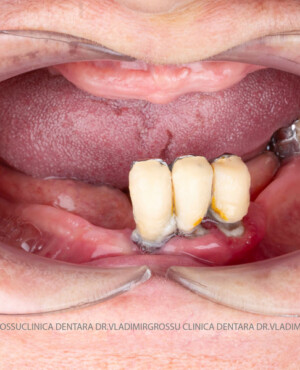

Această metodă este indicată pacienților cu edentație totală sau cu lipsuri dentare multiple, când dinții rămași nu mai pot susține o proteză fixă eficientă. Procedura se desfășoară în două etape:

- Prima etapă constă în inserarea implanturilor și fixarea unei proteze provizorii, realizate de obicei din masă plastică frezată, ce este montată în a doua sau a treia zi postoperator. Suturile sunt îndepărtate după 5-7 zile.

- A doua etapă are loc la aproximativ 6 luni după intervenție, când se realizează proteza definitivă, care este fixată pe implanturi prin intermediul unor piese numite multiunit-uri. Această etapă presupune lucrul la nivelul multiunit-urilor, nu direct pe implanturi, reducând astfel riscul de complicații.

Caz 1